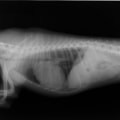

症例1:【マルチーズ 12歳齢 去勢オス】

B:胸部レントゲン写真 側面像

胸部レントゲン検査において重度の心拡大と肺水腫が認められた。超音波検査では、重度の僧帽弁閉鎖不全症、三尖弁閉鎖不全症、中程度の大動脈弁閉鎖不全症を合併していることが判明した。三尖弁逆流速度から肺高血圧症が示唆された。